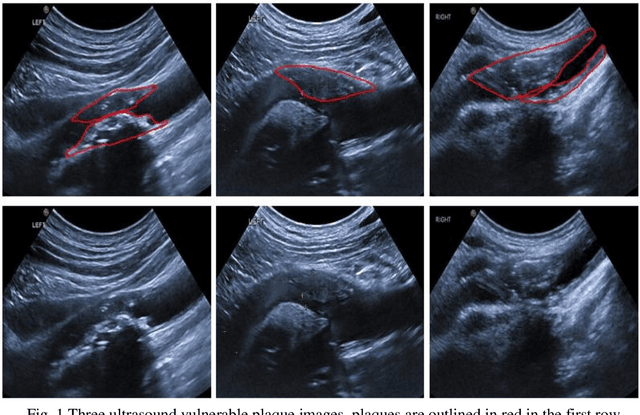

Abstract:Carotid arteries vulnerable plaques are a crucial factor in the screening of atherosclerosis by ultrasound technique. However, the plaques are contaminated by various noises such as artifact, speckle noise, and manual segmentation may be time-consuming. This paper proposes an automatic convolutional neural network (CNN) method for plaque segmentation in carotid ultrasound images using a small dataset. First, a parallel network with three independent scale decoders is utilized as our base segmentation network, pyramid dilation convolutions are used to enlarge receptive fields in the three segmentation sub-networks. Subsequently, the three decoders are merged to be rectified in channels by SENet. Thirdly, in test stage, the initially segmented plaque is refined by the max contour morphology post-processing to obtain the final plaque. Moreover, three loss function Dice loss, SSIM loss and cross-entropy loss are compared to segment plaques. Test results show that the proposed method with dice loss function yields a Dice value of 0.820, an IoU of 0.701, Acc of 0.969, and modified Hausdorff distance (MHD) of 1.43 for 30 vulnerable cases of plaques, it outperforms some of the conventional CNN-based methods on these metrics. Additionally, we apply an ablation experiment to show the validity of each proposed module. Our study provides some reference for similar researches and may be useful in actual applications for plaque segmentation of ultrasound carotid arteries.